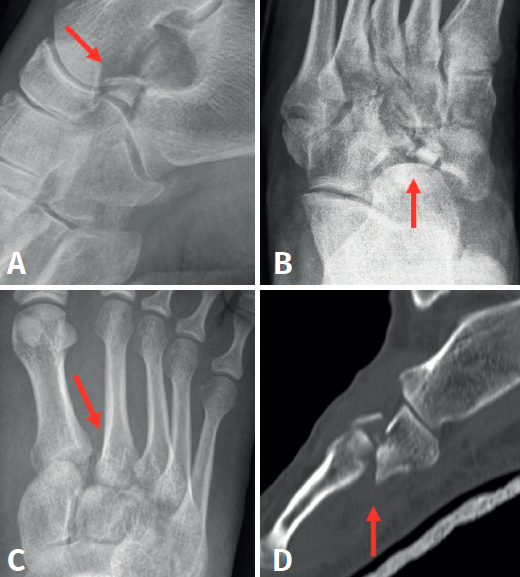

La edad media de la serie presentada es de 45 años (rango: 21-69 años). El seguimiento medio fue de 22 meses (rango: 12-65 meses). El mecanismo de acción de las fracturas fue, en 7 casos (53,8%), un traumatismo de alta energía tras accidente de tráfico, y, en los 6 casos restantes (46,2%), caída casual asociada a torsión de tobillo. Ninguna de estas fracturas se diagnosticó de forma aislada (Figura 2), objetivándose fractura de la pars anterior y cuerpo de calcáneo en 6 casos (46,2%), fractura de escafoides tarsiano en 4 casos (30,8%), en 2 casos (15,7%) lesión del complejo ligamentoso de Lisfranc y 1 caso (7,6%) de fractura-luxación de la base de los metatarsianos cuarto y quinto (Tabla 1).

En cuanto a las lesiones asociadas, Sharma et al.(1), detectan 12 casos de fractura en cascanueces de cuboides, 10 hombres y 2 mujeres, siendo la edad media de 20,2 años (14-32 años) y un seguimiento medio de 12,7 meses (6-22). Al igual que en nuestro estudio, no se encontró ninguna fractura de cuboides aislada. Entre las lesiones asociadas del pie incluyeron fracturas-luxación en la columna medial en 6 casos (50%), fractura de calcáneo en 3 casos (25%) y lesión de Lisfranc en 3 (25%). En cambio, en nuestro estudio, las fracturas de la pars anterior y cuerpo de calcáneo fueron las más prevalentes en 6 casos (46,1%), seguidas por fractura de escafoides tarsiano en 4 casos (30,8%); en 2 casos (15,7%), lesión del complejo de Lisfranc y 1 caso (7,6%) de fractura-luxación de la base de los metatarsianos cuarto y quinto. Estos hallazgos hacen necesaria, en el momento del diagnóstico, la realización como prueba complementaria de una TC del retropié y el mediopié tanto para el estudio morfológico de la fractura de cuboides como para descartar la presencia de las lesiones asociadas descritas(7).

Bien debido a la sutileza de las imágenes radiográficas, bien por el propio desconocimiento por parte del facultativo de este tipo de lesión y de las graves complicaciones que puede desarrollar, 6 de las 13 fracturas en cascanueces de cuboides de nuestra serie (46,1%) no fueron detectadas precozmente en Urgencias. Por ello, debe extremarse la atención ante pacientes que han sufrido un accidente de tráfico con lesión en el pie o un traumatismo en el que el mecanismo lesional haya sido el de caída de cierta altura asociado a torsión del pie o el tobillo. En caso de discrepancia clínico-radiográfica, será necesaria la realización de otras pruebas complementarias como TC o resonancia magnética con el fin de que estas fracturas potencialmente graves no pasen desapercibidas.